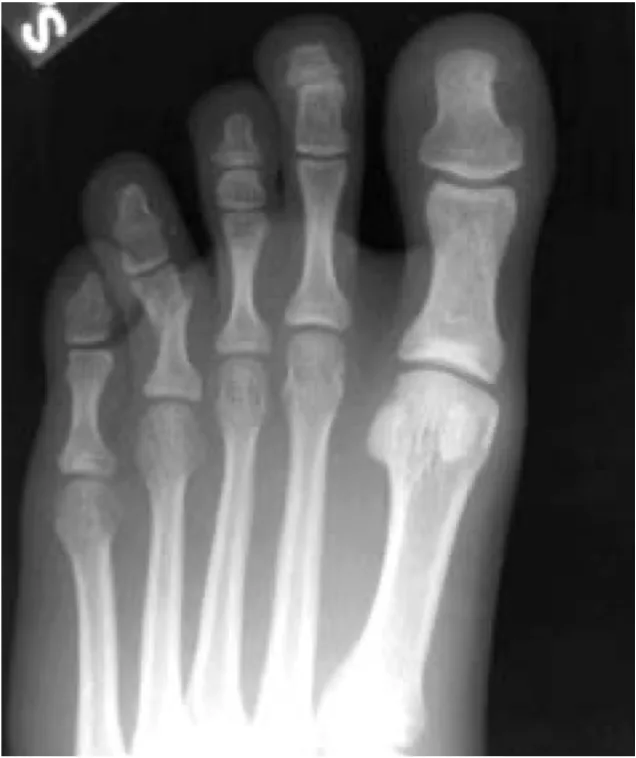

第4足趾の基節部に裂創があり, 前医で縫合されていましたが, X線写真を見ると裂創の下で基節骨が骨折してずれていました。

骨折した骨を元の形に戻して, 針金(鋼線)を刺し込んで固定する手術(経皮的鋼線刺入固定術)が必要な状態でしたが, 開放骨折のため感染リスクを考慮し, 数日経過を観察してから手術を行う方針としました.